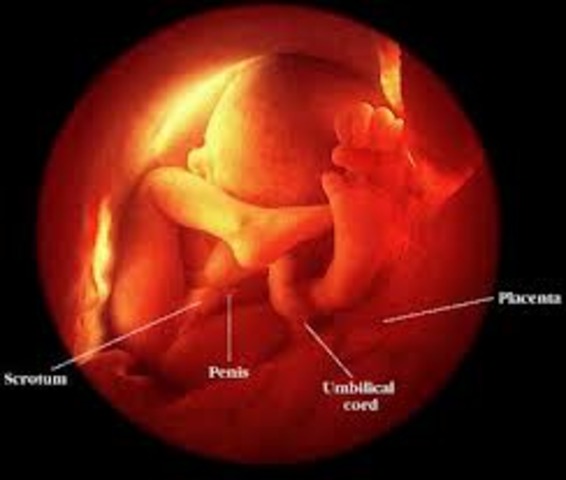

• Month 5

Month 5

• The baby is now 6 1/2 to 7 inches long, weighing about 4 to 5 ounces.

• The baby's hair, eyelashes, and eyebrows are appearing.

• The baby's teeth are continuing to develop.

• The baby's organs are maturing.

• The baby is becoming more active.